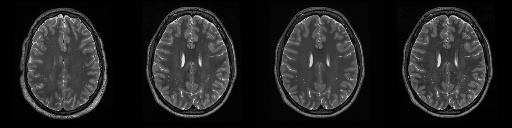

HCP T2w dataset

We utilize images from the publicly available Human Connectome Project (HCP) [51] T2-weighted (T2w) images dataset for the task of compressed sensing, which contains brain images from 47 patients. The HCP dataset includes cross-sectional images of the brain taken at different levels and angles.

Compressed sensing

We train a flow-based model from scratch on 10,000 randomly sampled images, utilizing the ncsnpp architecture [9] with minor adaptations for grayscale images. We employ compression rates , meaning . The measurement operator is given by a subsampled Fourier matrix, whose sign patterns are randomly selected. We evaluate our reconstruction algorithm’s performance on 200 randomly sampled test images.

We present the quantitative and qualitative results of compressed sensing in Tab. 1 and Fig. 4, respectively. As shown in Tab. 1, our method consistently achieves the best performance across varying compression rates . In Fig. 4, our method produces reconstructions that are more faithful to the original images, with fewer artifacts, leading to higher accuracy and clearer details.